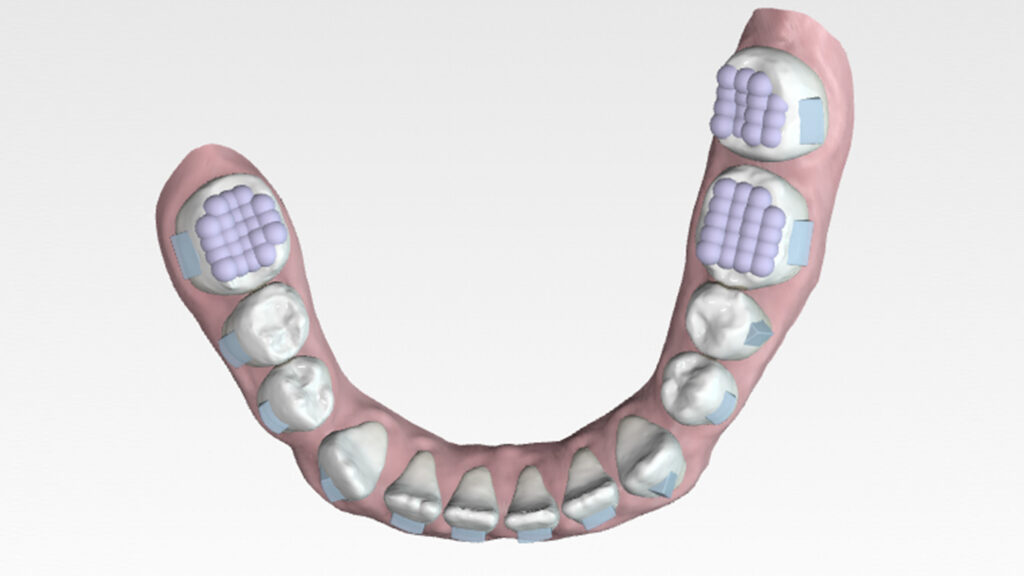

Once the transverse discrepancy was corrected, treatment continued with Spark Aligners to address the vertical plane. The planned vertical correction involved extruding the upper anterior teeth, with 1.7 mm of extrusion in the upper arch, and 1.5 mm in the lower arch using attachments. To assist in bite closure, turbo bites were employed to intrude the mandibular molars.

Initial

Post-disjunction

First set of aligners

As shown in the accompanying images, the planned vertical correction was fully achieved. At this stage, provisional composite veneers were placed from canine to canine in the upper arch to enhance the patient’s aesthetics and compensate for Bolton’s discrepancy.